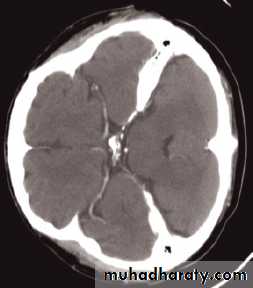

Enlargement of ventricles

There are two basic mechanisms which cause the cerebral ventricles to enlarge:• Obstruction to the CSF pathway, either within the ventricular system (non-communicating hydrocephalus) or over the surface of the brain (communicating hydrocephalus)

• Secondary to atrophy of brain tissue